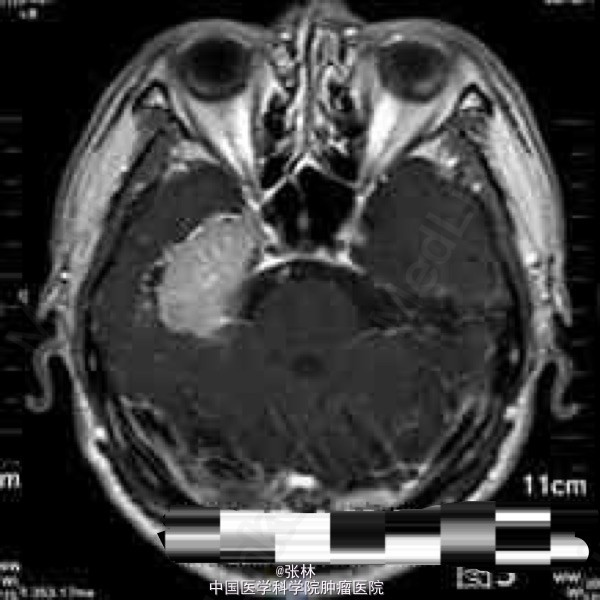

CT表现:右侧颅中窝可见一不规则肿块,呈等密度,内部密度均匀,CT值约37HU,肿块边界尚清晰,略成分叶状,与邻近骨质呈广基底相连,最大截面3.3cm×3.8cm,边缘处可见带状低密度影,边界清晰,CT值约16HU。肿块周边脑组织水肿,密度略减低。肿块周边骨质未见增厚硬化或变薄等异常改变(图1-2)。 CT诊断:右侧颅中窝肿块,伴周围脑组织水肿,建议进一步检查。 MRI表现:右侧颅中窝可见一不规则肿块,最大截面3.6cm×4.1cm,肿块边界清晰,成分叶状,与邻近骨质呈广基底相连(图5-6),在T1WI上呈等信号,在T2WI上呈略高信号;肿块边缘可见不规则液性信号带,在T1WI上呈低信号,在T2WI上呈高信号,与脑组织分界清楚(图3-4);肿块前方颞叶部分脑组织可见片状异常信号,在T1WI上呈稍低信号,在T2WI上呈略高信号,边缘模糊(图3-4);注射对比剂后,肿块实性部分明显强化,并可见“脑膜尾征”,而液性信号带未见强化(图5-6),肿块前方颞叶的片状异常信号未见强化。 MRI诊断:右侧颅中窝脑膜瘤,部分囊变,伴周围脑组织水肿。 手术病理结果:非典型性脑膜瘤,WHO分级II级。 讨论: 脑膜瘤是颅内仅次于胶质瘤的常见原发肿瘤,发病率占颅内肿瘤的16%~17%,在颅内脑外原发肿瘤中占第一位。它起源于脑膜的蛛网膜内皮细胞,常见于富含蛛网膜颗粒与蛛网膜绒毛的地方,以上矢状窦旁、大脑凸面、大脑镰、蝶骨嵴、鞍结节、嗅沟、小脑桥脑角区及小脑幕等部位多见。